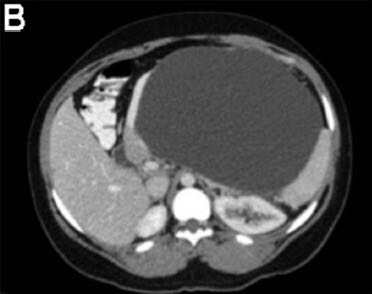

3个月前,她被电击中摔伤了腹部。当时这引起了上腹部疼痛;然而,她没有立即去医院直到3个月后才就诊。 该患者之前没有明显的病史或手术史,是一个非吸烟者,偶尔饮酒。 身体检查发现该女性健康,营养状况良好,唯一值得注意的是,腹部浅触诊时可于上腹部触及一个明显的肿块。 血常规检查包括全血细胞计数,尿素氮,电解质,葡萄糖,以及肝功能检查,均在正常范围内。血清淀粉酶66U/L,白蛋白43g/L,HIV 1/2 Ab/Ag酶联免疫吸附试验为阴性。 腹部对比增强计算机断层扫描显示连续轴向截面如图A-D。图E为矢状面。 剖腹手术时吸出低黏度,清澈,囊液,囊液生化分析显示,淀粉酶58903U/L,乳糖脱氢酶904U/L,蛋白质<10g/L。未获取囊性癌胚抗原和CA-19-9。在剖腹手术时对多个囊壁活检取样(图F)。

计算机断层扫描证实源自胰尾的一个大型,单房,囊性肿块,伴未分隔的附壁结节,或囊性钙化。影像学结果,临床病史,和囊液分析支持胰腺假性囊肿的诊断。出人意料的是,囊壁活检显示为良性粘液分泌柱状上皮,雌激素受体阳性,与良性粘液性囊壁肿瘤(MCN)一致。最终,执行远端胰腺切除术,并且此后恢复良好。鉴于MCNs已经确定的恶变可能(6%-27%的病例),这例患者“有惊无险”,按照计划因假囊肿接受胰囊肿胃吻合引流术可以避免恶性肿瘤转化的严重后果。